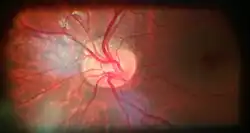

Optic disc edema and haemorrhage